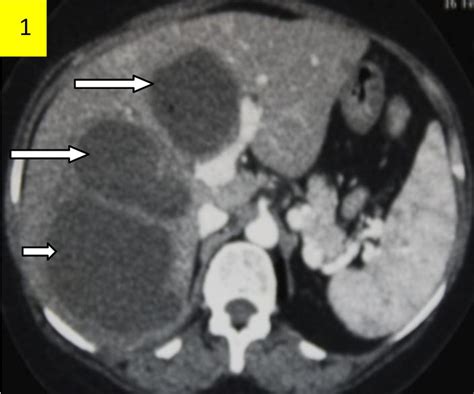

Diagnosing a liver abscess involves a combination of medical history, physical examination, and diagnostic tests. Imaging studies such as ultrasound, CT scans, and MRI are commonly used to visualize the abscess. Blood tests can help identify the underlying infection, and sometimes, a sample of the abscess fluid may be taken for culture and sensitivity testing.